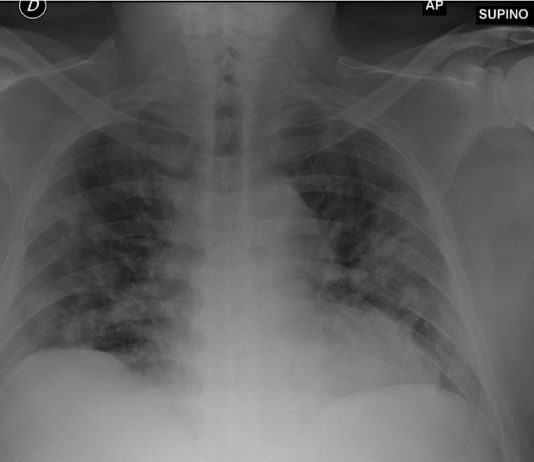

68-year-old male

with fever, dyspnea and diarrhea for 7 days. Blood test: leukocytosis, increased C-PR, procalcitonin in

the range. Medical history: chronic lymphocytic leukemia under follow-up,

dyslipidemia and HTA.

Chest radiography: